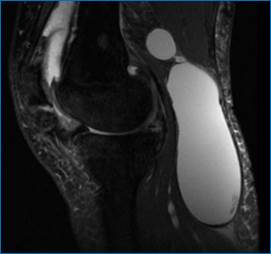

Рис. 1. Выпот в полости сустава, утолщение синовиальной оболочки

Зачастую может быть обнаружен выпот в полости того или иного сустава (рис. 1).

Рис. 5. Киста Бейкера (МРТ- картина разрыва капсулы)